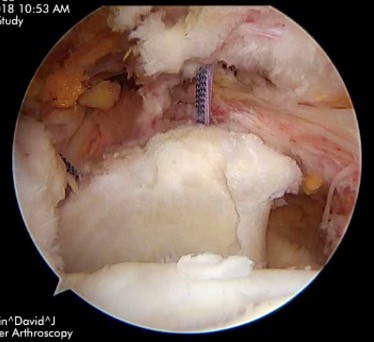

SUPERIOR CAPSULAR RECONSTRUCTION

This is a technique that was developed in Japan and utilizes a tissue graft to replace the lining of the rotator cuff (superior capsule) that provides stability to the shoulder. Though it doesn’t replace the active muscle component of the cuff, it does compensate for some of the rotator cuff function. A big advantage of this surgery is the ability for it to be performed using minimally invasive arthroscopic techniques. The recovery period is typically more extensive with a greater emphasis on physical therapy. Results so far have been very promising and performed with greater frequency in the United States.

AFTER SUPERIOR CAPSULAR RECONSTRUCTION